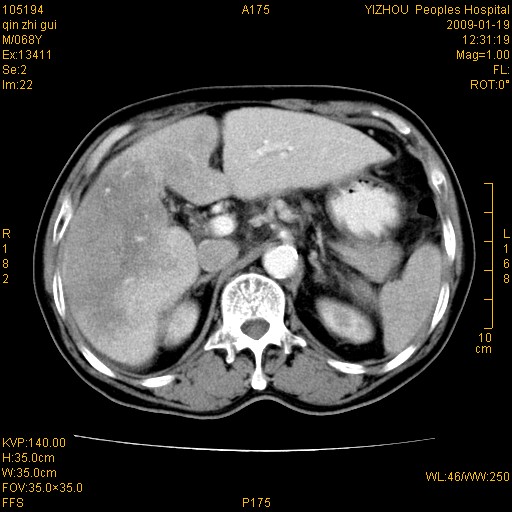

以下是引用随光逐影在2009-1-21 16:11:00的发言:[br]1)考虑肝右叶肝癌并肝静脉及门静脉瘤栓形成。2)肝硬化,少量腹水。3)胆囊炎。4)右侧少量胸腔积液。

病灶外缘凹凸不平,平扫低密度,增强动脉期有强化,门脉早显,静脉期及延期呈延迟强化,结合病史考虑右肝前叶巨块型肝癌可能性大,强化表现不除外胆管细胞癌